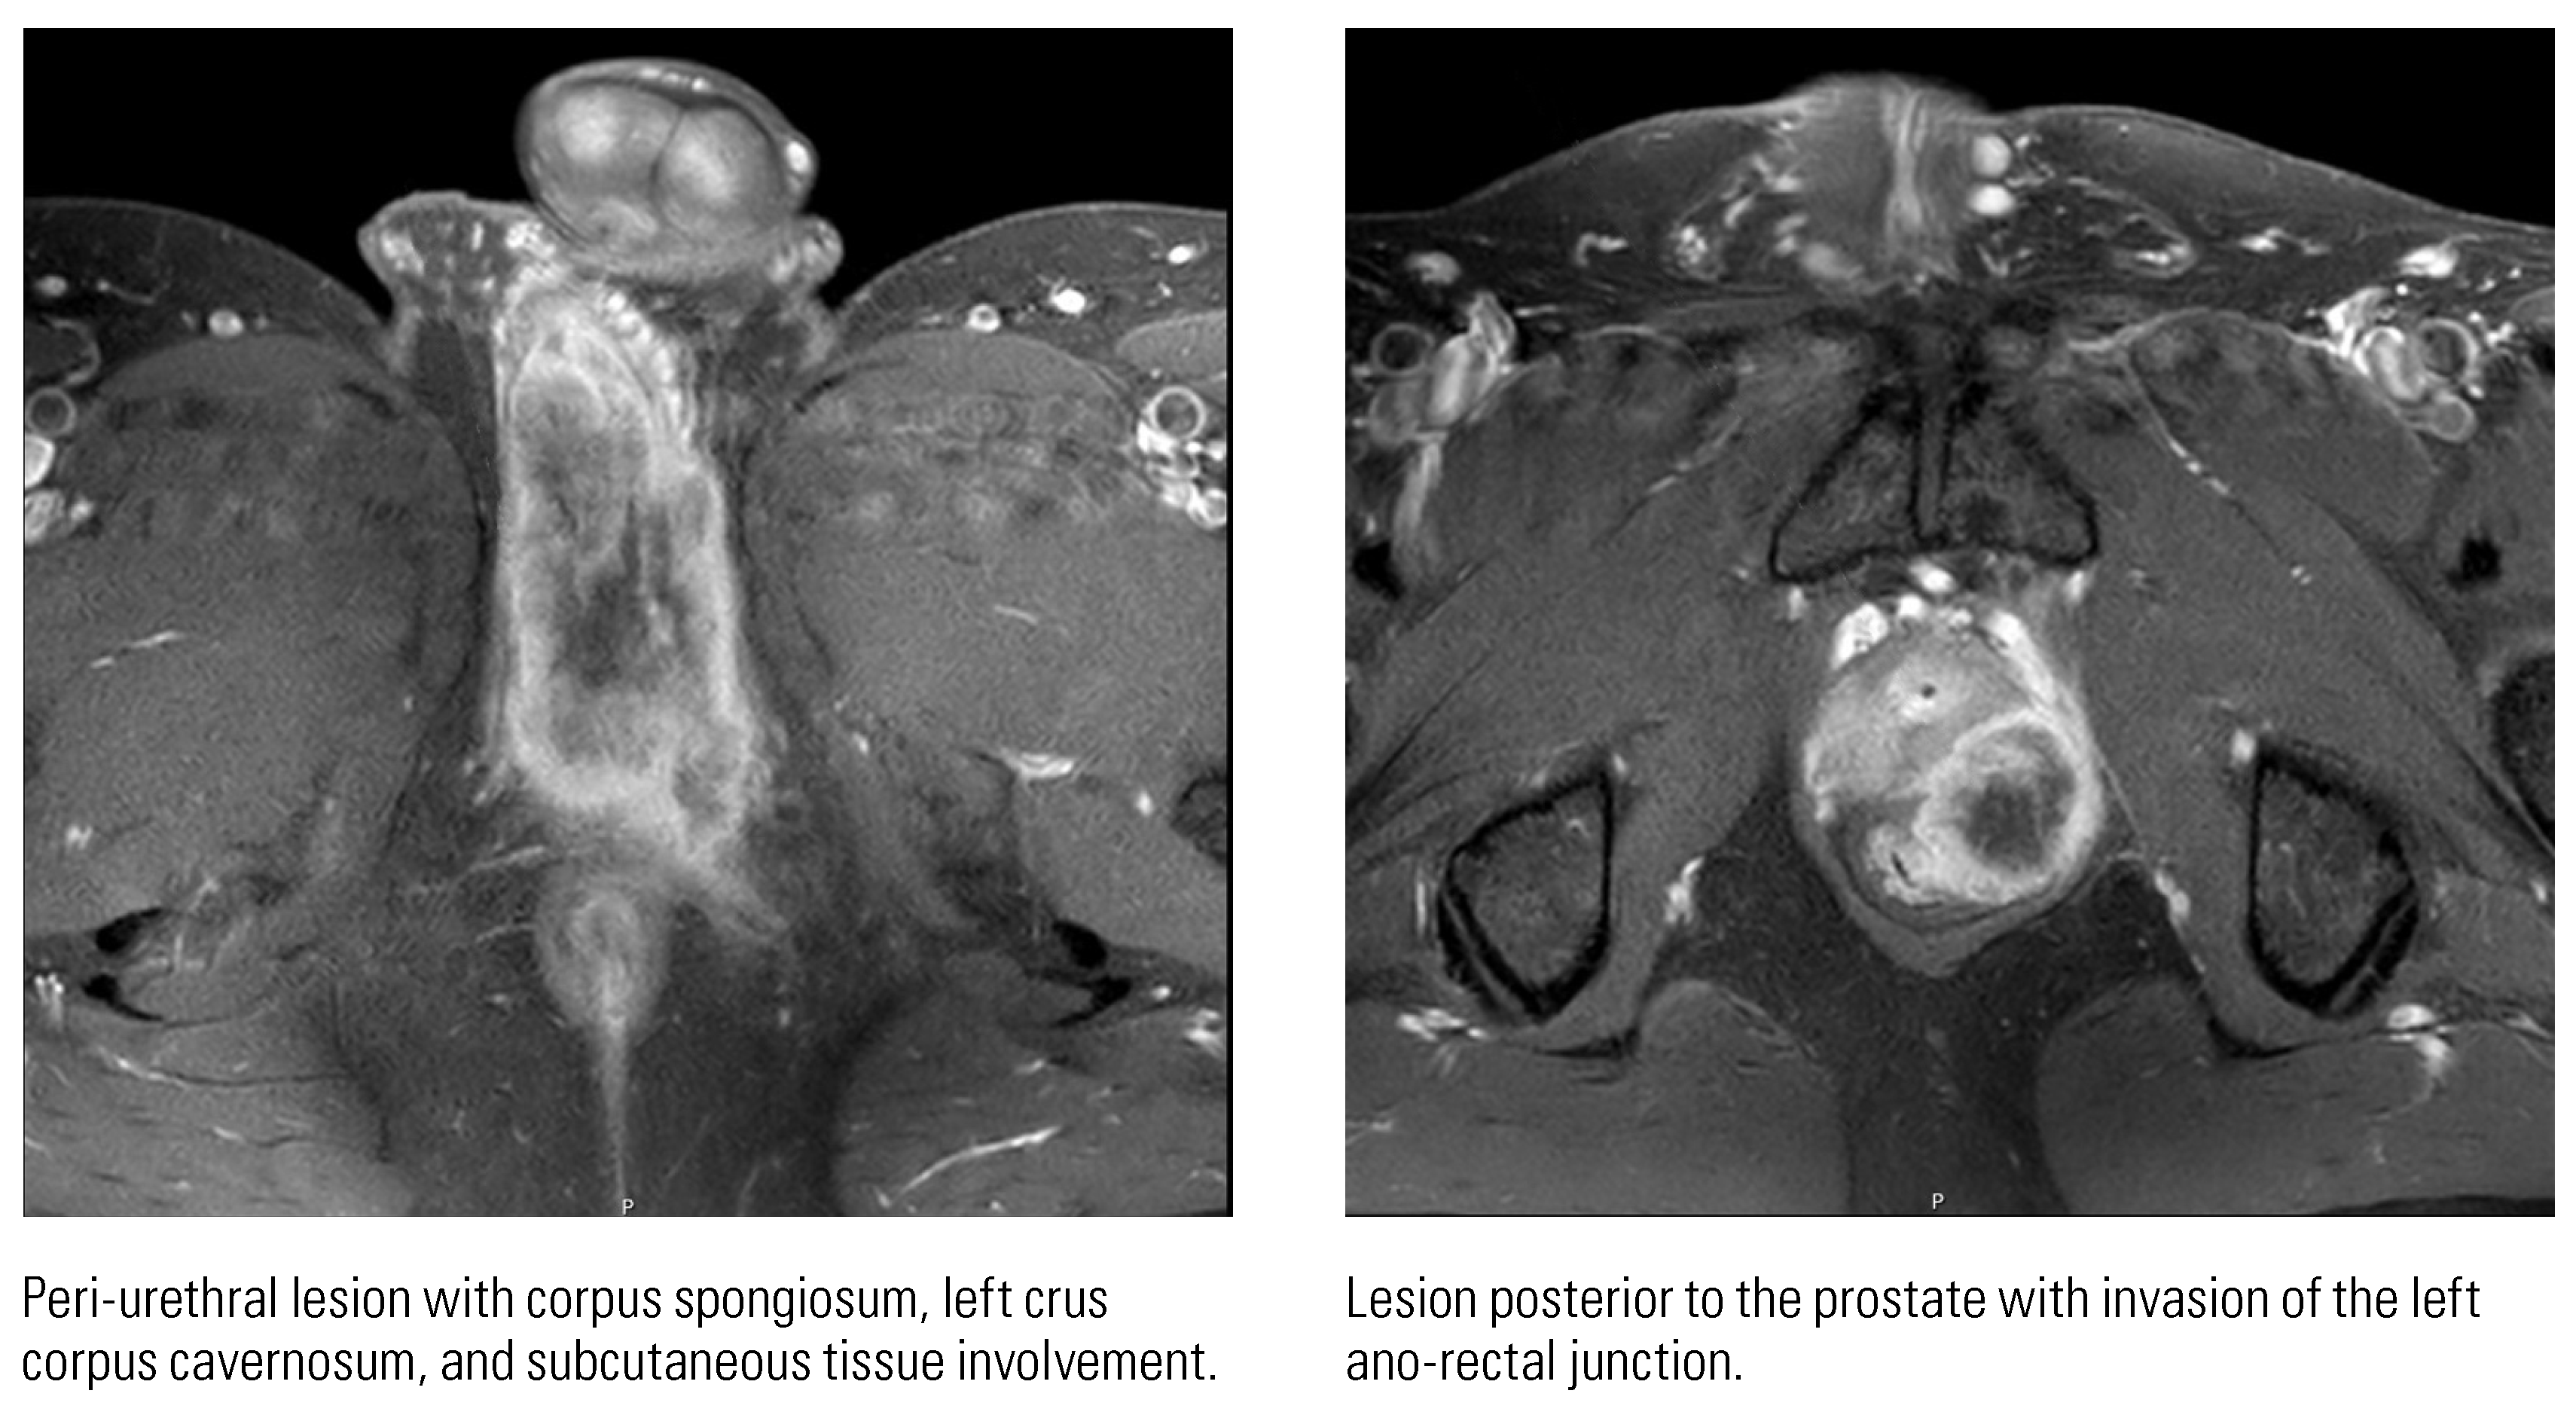

Down the Not So Straight and Narrow: A Rare Case of Primary Urethral Squamous Cell Carcinomas in a Young Patient